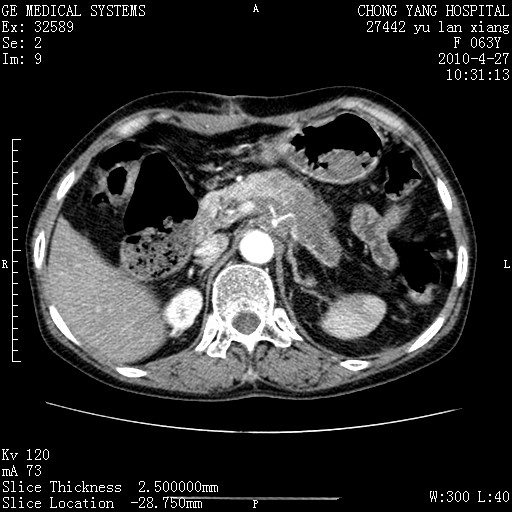

标题: CT26066:F63Y 上腹正中压痛半月,CA199:7400u/ml,MR示胰腺炎伴 [打印本页]

胰腺癌侵犯腹腔动脉干-分支、胃壁、左侧膈肌伴胰周及腹膜后淋巴结转移、胆囊切除术后。

胰腺癌侵犯腹腔动脉干-分支、胃壁、左侧膈肌伴胰周及腹膜后淋巴结转移、胆囊未显影。